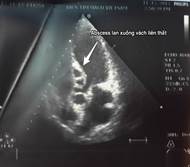

Kết quả siêu âm tim qua thành ngực cho thấy hình ảnh sùi van động mạch chủ, áp xe thành trước động mạch chủ lan tới 1/3 trên vách liên thất gây hở chủ nhiều. Sùi van hai lá gây hở hai lá nhiều và giãn các buồng tim (Hình 1,2). Điện tim đồ cho thấy block nhĩ thất cấp 3 (Hình 3). Cấy máu cấp ở 3 vị trí khác nhau cho kết quả âm tính. Bệnh nhân được hội chẩn nội – ngoại khoa và được chỉ định phẫu thuật cấp cứu.

| Hình 1,2: Hình ảnh abscess gốc ĐMC và vách liên thất trên siêu âm tim. | |